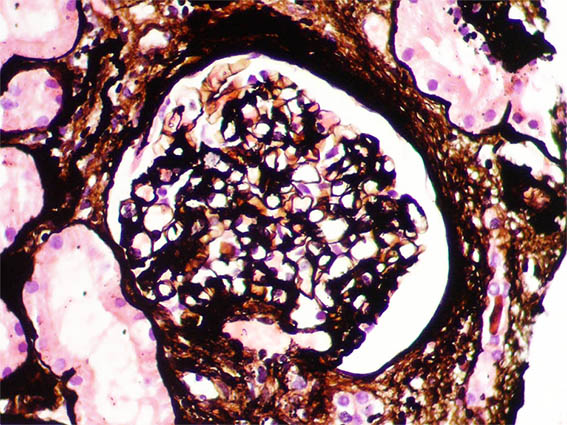

Figure 6. Methenamine-silver stain, X200.